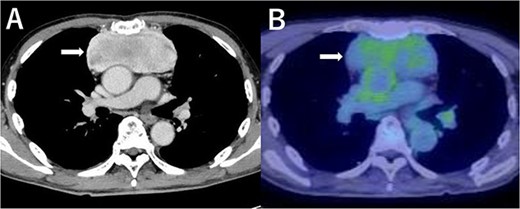

A 79-year-old man was referred to our hospital with an abnormal shadow on chest X-ray. He had a history of light smoking (3 pack-years) with no major past medical history. Physical examinations and laboratory tests, including tumor markers, were unremarkable. The chest CT revealed the presence of an anterior mediastinal mass, which had its longest diameter being 11 cm. The mass compressed adjacent great vessels and the heart posteriorly. On contrast-enhanced magnetic resonance imaging scan, the tumor presented as a well-demarcated, homogenously enhanced mass, and the direct invasion into surrounding structures was not apparent. Positron emission tomography (PET)-CT scan revealed a slight uptake of fluorodeoxyglucose (FDG) by the tumor (standardized uptake value [SUV] max = 3.32) and no signs of metastases (Fig. 1). Thymoma, thymic cancer, thymic neuroendocrine tumor or malignant lymphoma was suspected. However, ultrasound-guided percutaneous needle biopsy through the anterior chest wall revealed an undifferentiated sarcoma.

Contrast-enhanced chest CT scan (A) and FDG-PET scan (B) of the tumor (SUVmax = 3.32).